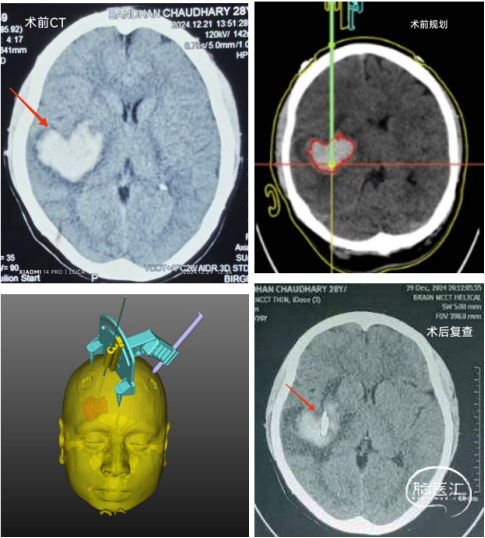

29日BIR医院使用中国原创技术为一位28岁的尼泊尔脑溢血偏瘫患者顺利施行定位导向微创手术,手术取得良好疗效。

依次是术前CT的心形血肿,术前的平面规划和手术设计,以及术后的CT复查,显示引流管成为精准命中靶心的“丘比特之箭”